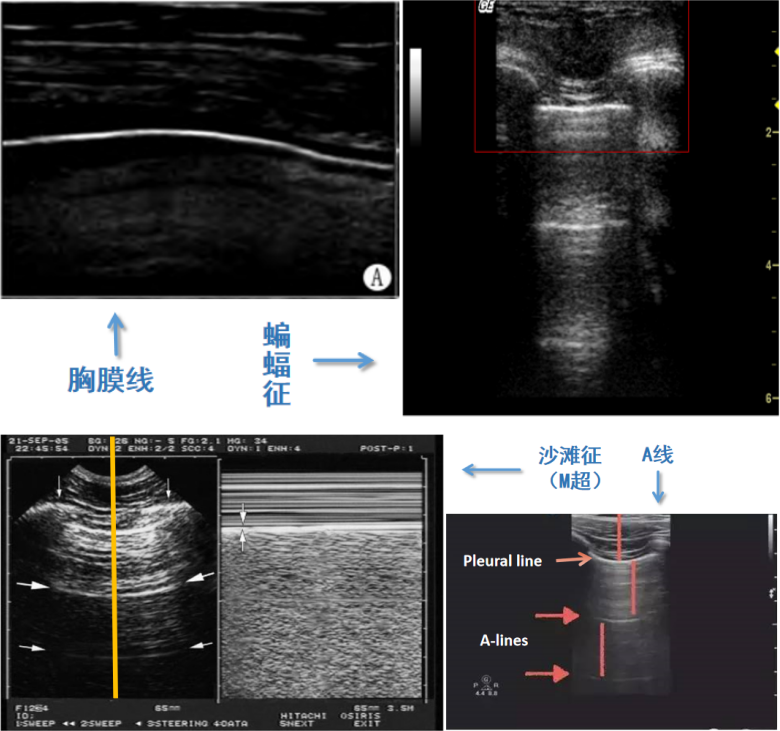

在了解异常肺超征象之前,应该先要知道正常肺部超声征象。进行肺部超声检查时,首先要确定胸膜的位置。将探头置于两个肋骨之间时,会看到屏幕外围两侧有宽约2 cm,厚约0.5 mm的高回声曲线,即胸膜线。正常的胸膜线是清晰、锐利、光滑、连续的。胸膜线位于屏幕中央,两侧肋骨下方,其形态类似蝙蝠,故称为“蝙蝠征”。还有肺滑动征(胸膜滑动征)、A线、M超模式下的沙滩征,这些都是正常肺部超声征象(图3)

图片

图3  正常肺部超声征象